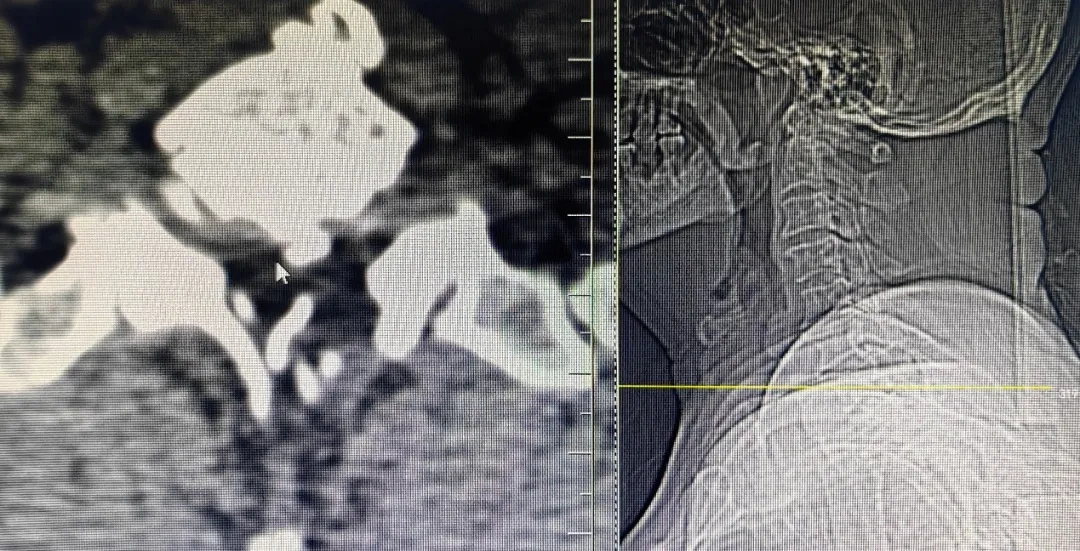

患者,男性,左上肢内侧疼痛剧烈,保守治疗无效,就诊于91直播 脊柱外科中心B区,诊断为神经根型颈椎病,C7/T1节段,左侧神经根管骨质增生严重,颈前路手术因胸骨阻挡难以实施,后路手术减压风险高、担心减压不彻底且创伤大。赵文奎博士了解患者病情后,用北医三院的诊疗理念,从影像学资料研判、诊断与鉴别诊断、治疗方案的制定等不同方面进行了详细分析,与91直播 脊柱外科中心B区医疗团队共同为患者制定了“精准化”手术方案——经皮内镜颈椎椎板切除神经根管减压术。

上图为术后复查CT

可见神经根管较术前变宽